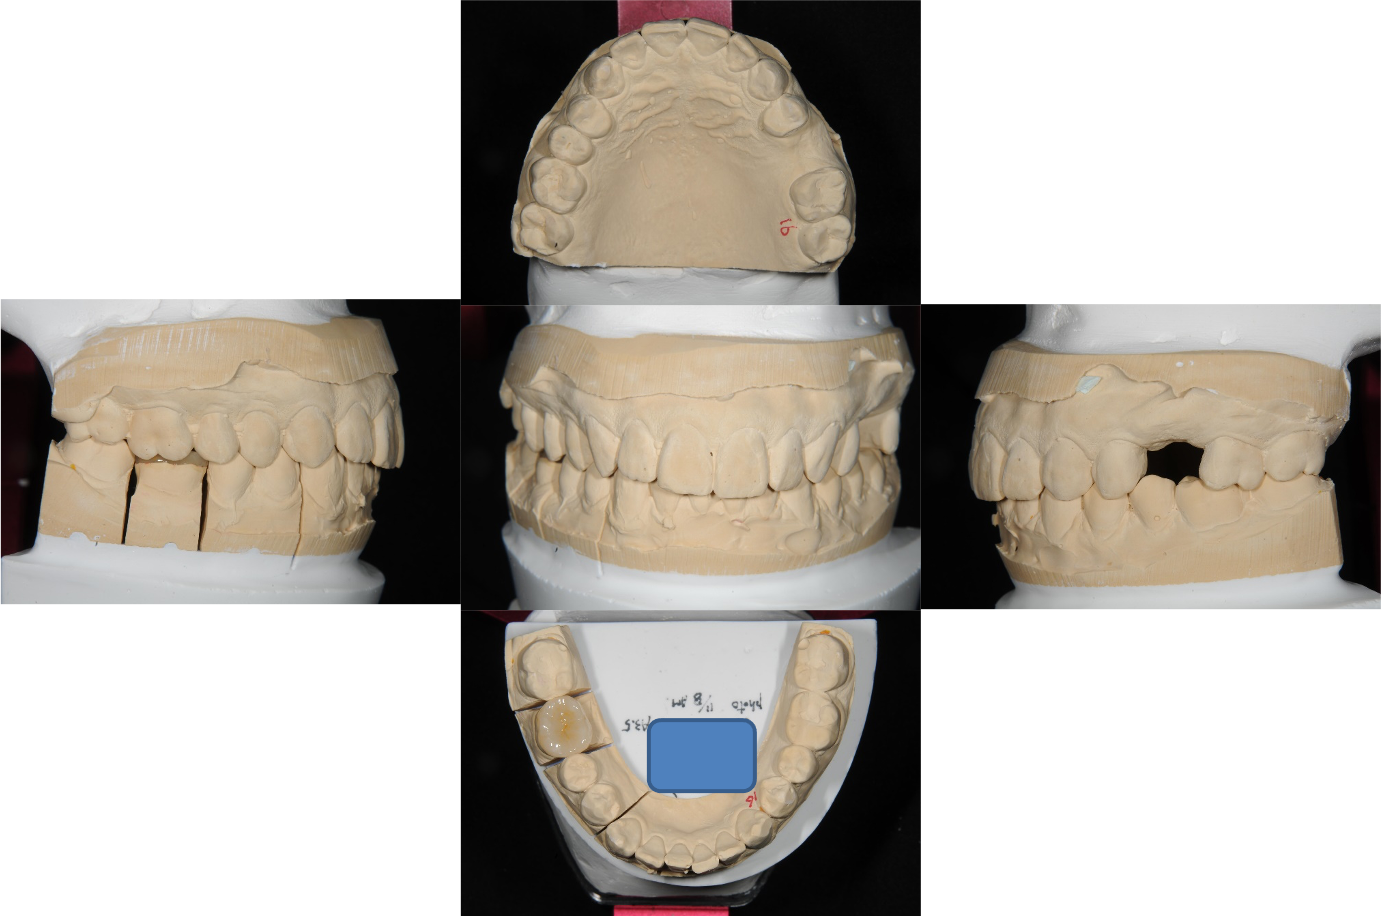

上面弓與咬合器

咬合器上製作陶瓷冠塊體

陶瓷冠塊體